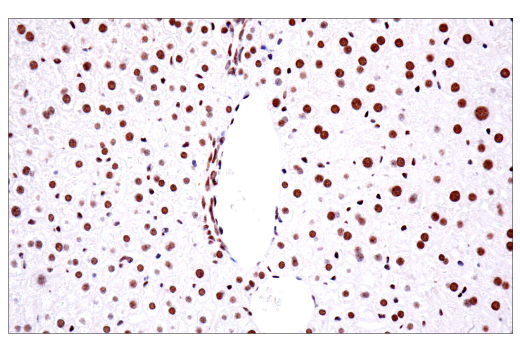

Immunohistochemical analysis of paraffin-embedded normal mouse liver using TDP43 (E2G6G) Rabbit mAb.

Immunohistochemistry Image 4: TDP43 (E2G6G) Rabbit Monoclonal Antibody